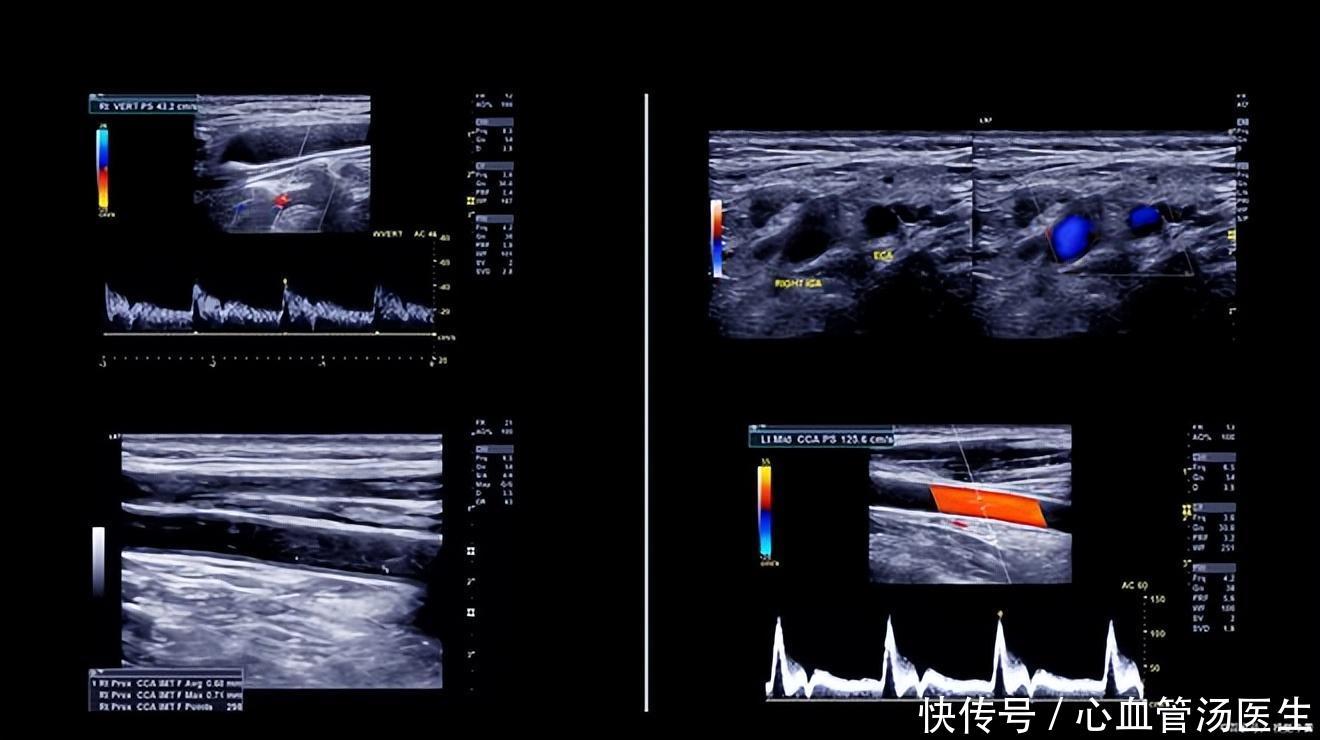

发现颈动脉斑块,哪些人可以不吃药?这些方法有助于稳定斑块

颈动脉斑块